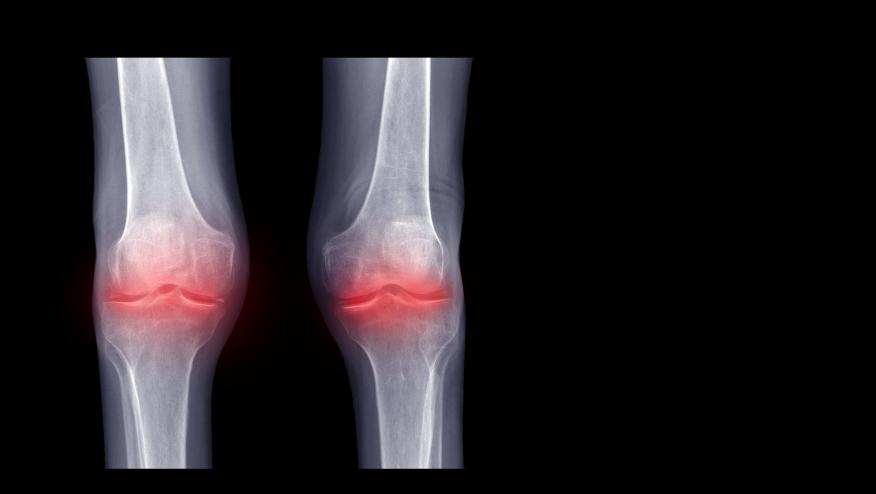

An international cohort study of patients with calcium pyrophosphate deposition (CPPD) disease, i.e., recurrent acute CPP crystal arthritis, chronic CPP crystal inflammatory arthritis, and crowned dens syndrome (CDS) identifies both acute and chronic inflammatory phenotypes, each with distinctive clinical and imaging diagnostic features.

CPPD disease has both acute and chronic inflammatory phenotypes, with specific features to be considered in the diagnostic workup.